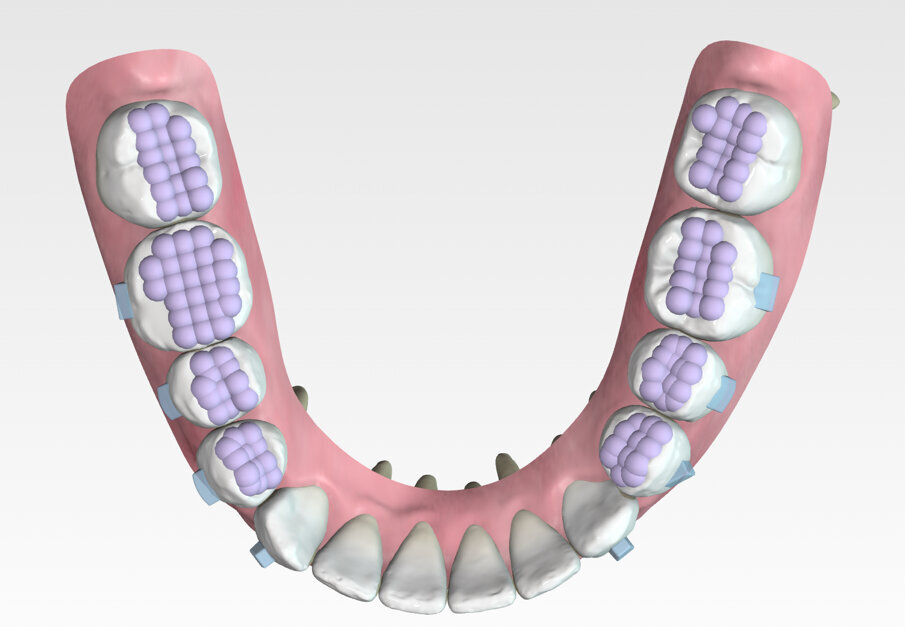

Specifically, the plan prescribed upper arch expansion and bilateral molar and second premolar intrusion of 3 mm. To support intrusion and prevent reciprocal lifting of the aligners, 4 mm wide occlusally beveled retentive attachments were designed and placed on the premolars. (Fig. 11)

The results presented in this case report demonstrate the potential for noninvasive, efficient, precision treatment with Spark Clear Aligners. Since treating this case, Spark has designed integrated occlusal intrusion turbos to enhance intrusion efficiency. (Fig. 25) These intrusion turbos, along with biting exercises, have the potential to further reduce the number of aligners required for treatment.